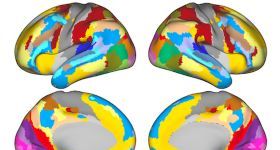

思影科技将于2025年6月27日--2025年7月1日(周五—下周二)在北京举办第六届Surface based fMRI分析专题班(详...

思影科技将于2025年6月27日--2025年7月1日(周五—下周二)在北京举办第六届Surface based fMRI分析专题班(详...